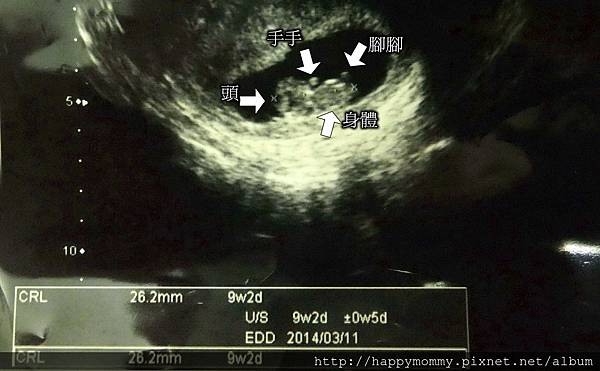

2013.08.08 超音波2

♥ 獨生子接納弟妹的歷程 - 慶哥哥的心情故事I - 媽媽懷孕了!